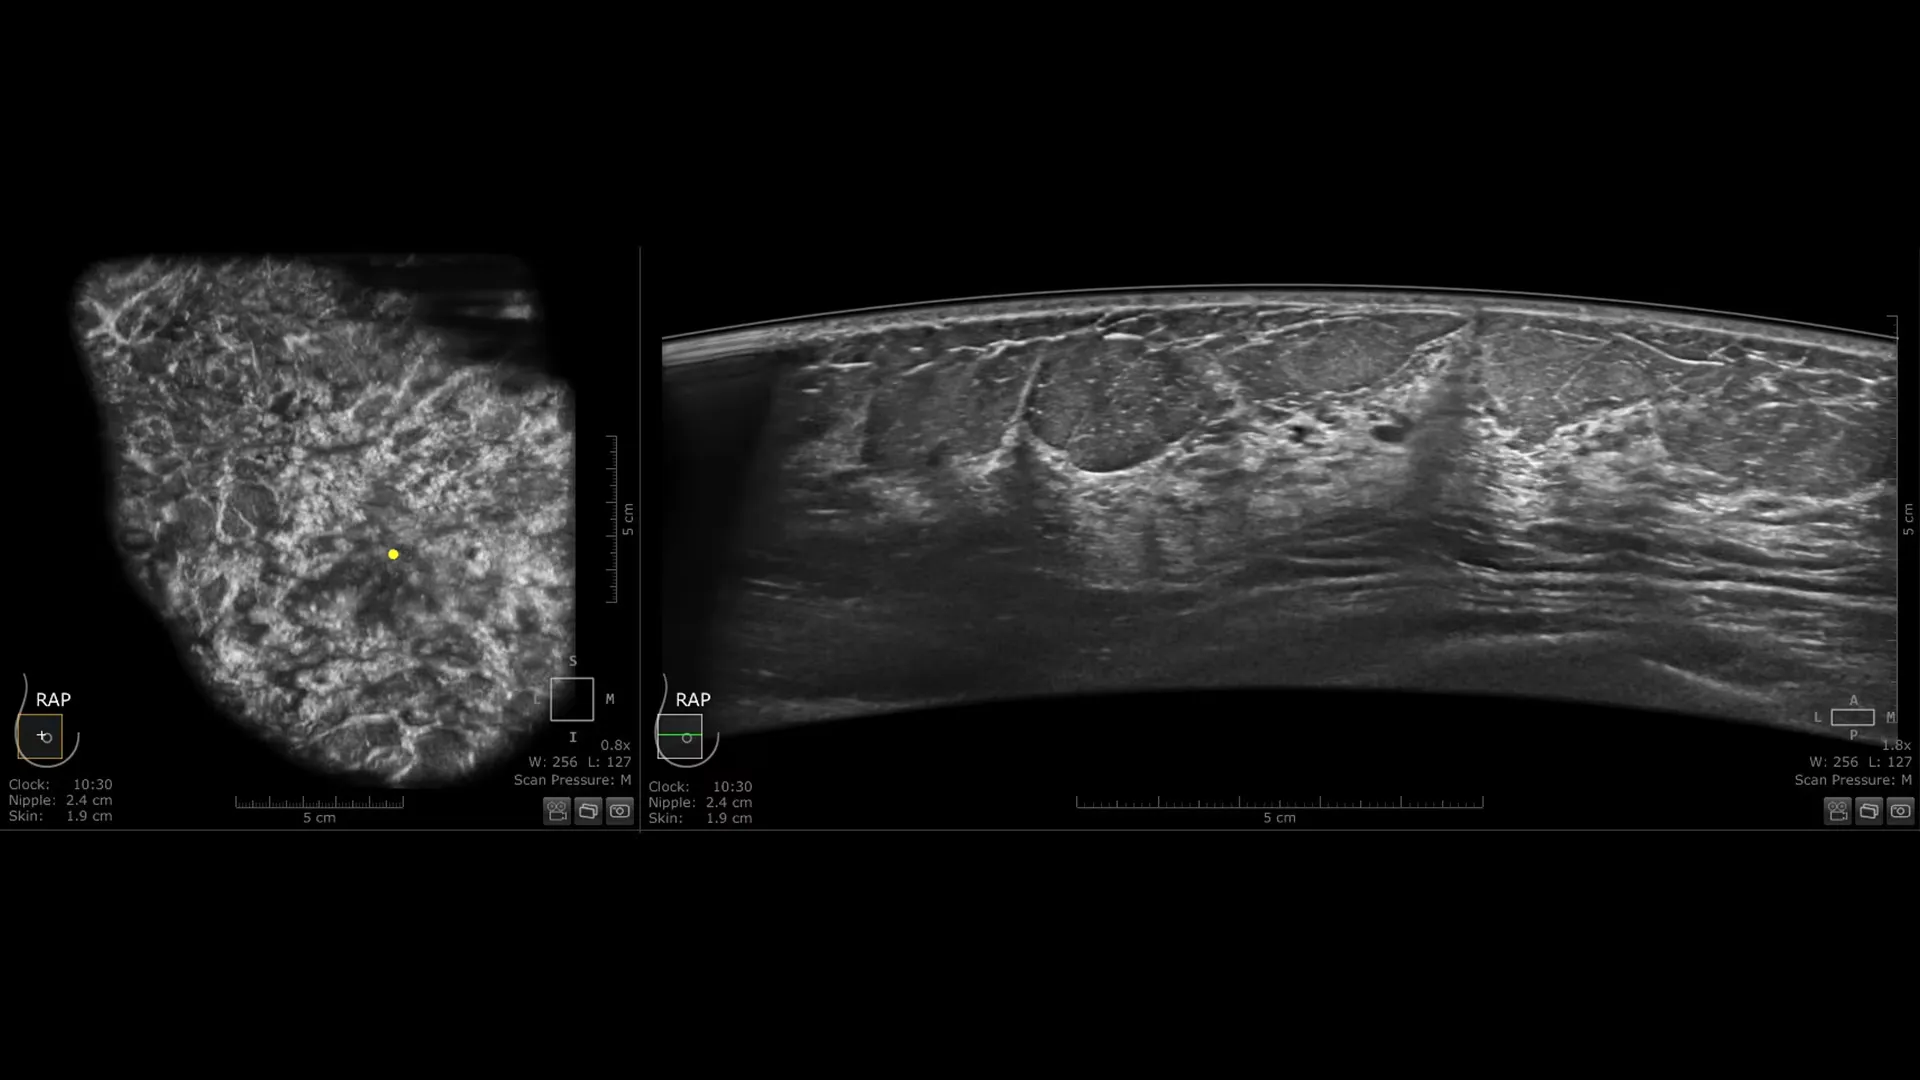

Invenia ABUS Premium: inovativno 3D ultrazvučno rješenje uz podršku umjetne inteligencije za pacijentice s gustim tkivom dojke

Invenia ABUS Premium osmišljen je za visoku propusnost pacijentica i iznimnu kvalitetu prikaza, pružajući visoku razinu dijagnostičke sigurnosti. Zahvaljujući inovativnom dizajnu, sustav je jednostavan za korištenje, reproducibilan, neovisan o korisniku, standardiziran te omogućuje očitanje nalaza s bilo koje lokacije.

Njezin blago zakrivljen oblik duljine 15,3 cm prati prirodnu konturu dojke, povećavajući udobnost pacijentice* i osiguravajući potpuni kontakt za sveobuhvatnu pokrivenost. Unaprijeđena kvaliteta prikaza* dodatno povećava dijagnostičku sigurnost pri očitanju ABUS pregleda.

- cSound Imageformer, softverska obrada slike, omogućuje iznimno precizan i ponovljiv prikaz zahvaljujući automatskom fokusiranju u svakoj točki slike